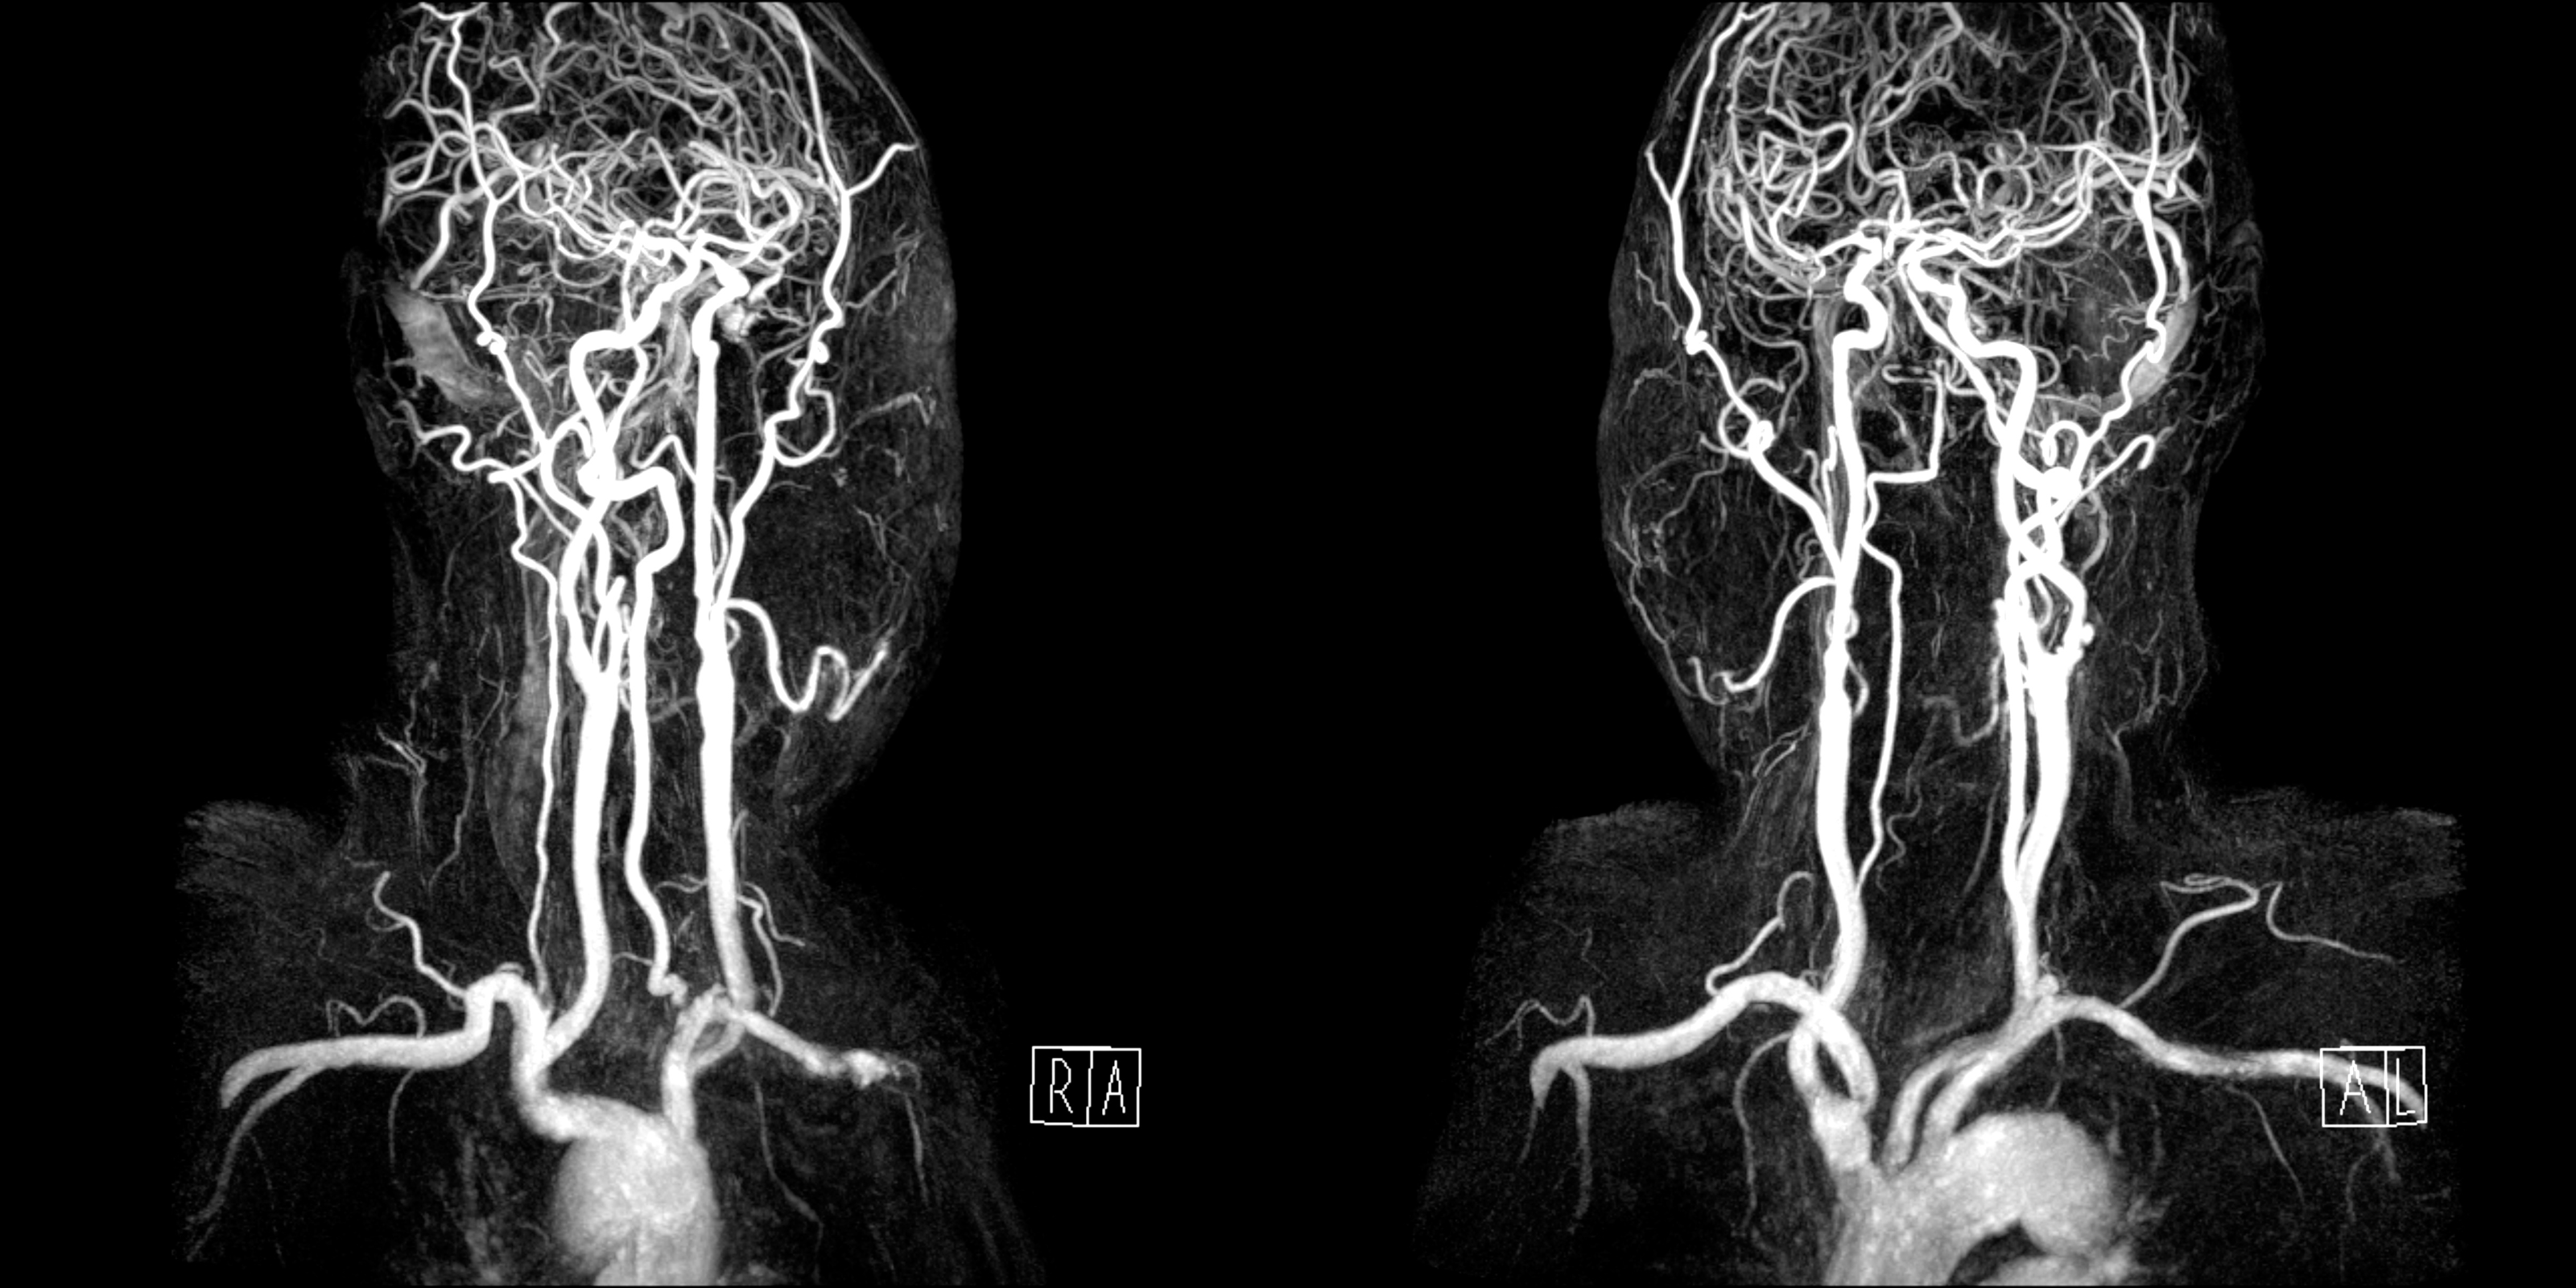

급성 좌측 안쪽 연수 부위 뇌경색(acute infarction in the left anteromedial medulla) 소견의 확산강조영상(diffusion-weighted image, DWI)

좌측 척추동맥과 양측 내경동맥의 협착이 확인된 자기공명 혈관조영검사(magnetic resonance angiography, MRA)